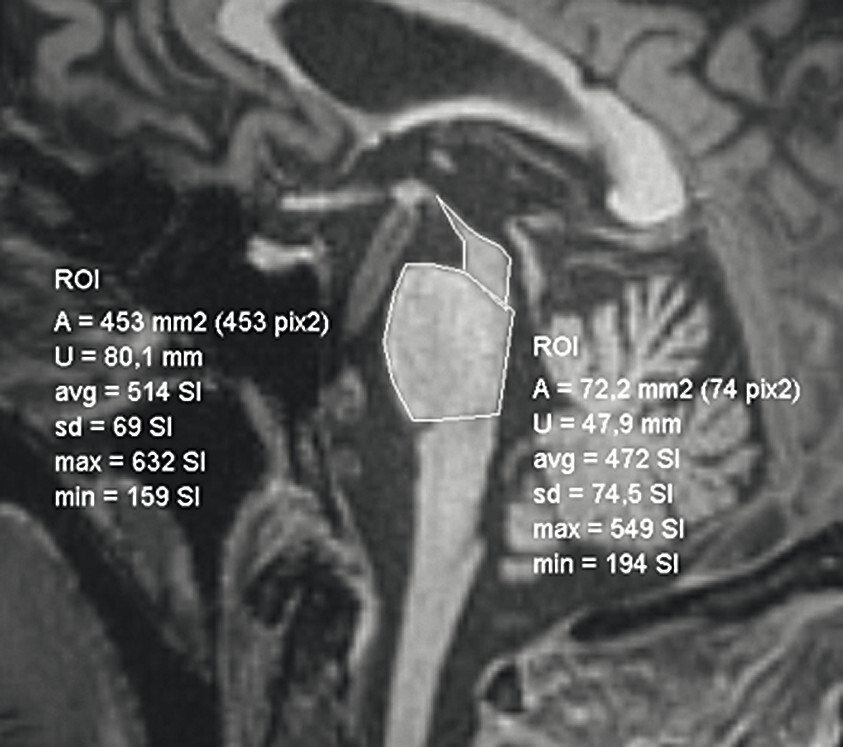

- Bei der Bestimmung der Midbrain/Pons-Ratio werden auf sagittalen Mittellinienaufnahmen Ellipsen in Pons (ohne Tegmentum pontis) und Mittelhirn gelegt und die kurzen Durchmesser der Ellipsen zueinander in Beziehung gesetzt. Bei Normalpersonen beträgt der kurze Mittelhirndurchmesser ca. ⅔ des kurzen Ponsdurchmessers, bei Patienten oder Patientinnen mit progressiver supranukleärer Blickparese ist er auf etwa 50% oder weniger erniedrigt, bei Personen mit Multisystematrophie vom zerebellären Typ auf über ⅔ erhöht [8].

- Für die Berechnung des MR-Parkinson-Indexes werden auf sagittalen Mittellinienaufnahmen Ponsfläche, Mittelhirnfläche und mittlerer Kleinhirnstieldurchmesser sowie auf koronaren T1w Aufnahmen der obere Kleinhirnstieldurchmesser bestimmt. Die Berechnung erfolgt entsprechend folgender Formel [1] [10]; ein Wert über 12,6 spricht für eine progressive supranukleäre Blickparese:

62-jähriger Mann mit über 3 Jahre zunehmender Bewegungsverlangsamung und unsicherem Gangbild. Die MP-RAGE-Aufnahmen zeigen eine deutliche Mittelhirnatrophie mit Kolibri- (a) und Mickey-Mouse-Zeichen (b). Das Mittelhirn/Pons-Verhältnis liegt mit 0,15 im pathologischen Bereich (Normalwert ca. 0,24). Die voxel- und regionenbasierte morphometrische Analyse (c) zeigt neben der Mittelhirnatrophie eine links-frontomesial betonte Atrophie, das FDG-PET (e) einen Hypometabolismus dieser Regionen. Dieses Muster ist typisch für eine sog. Tauopathie und unterstützt daher die Diagnose progressive supranukleäre Parese mit Richardson-Syndrom.

a Sagittale MP-RAGE-MRT-Sequenz.

b Axial reformatierte MP-RAGE-MRT-Sequenz.

c Planimetrische Messungen zur Bestimmung des MR-Parkinson-Index.